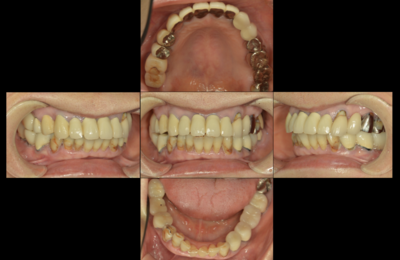

右下第二大臼歯、歯と歯の間に虫歯があり治療を行いました。 直接充填するダイレクトボンディングという方法で治療を行いました。 セラミックと比較して削る量が少ない、一回で歯が入るというメリットがありますが、口を開けている時間が長いというデメリットもあります。 治療する歯ができるだけ長持ちする治療法を提案するようにしています。 ダイレクトボンディング 残っている歯の溝や膨隆から、咬合面の形態をイメージし…